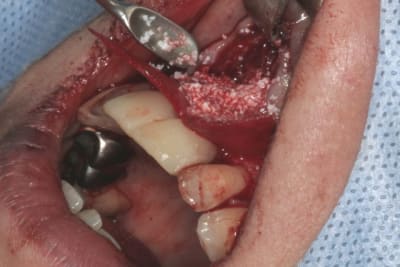

tien, ce matin, extraction de 24/25, curetage méticuleux, forage, comblement du gap, pose des 2 implants qui se sont bloqués à 50Ncm au CA sur les 3 ou 4 mm apicaux, pose des vis de cicat, sutures...35min....tranquille...

Purée, tu prends des risques énormes en fourrant ton bio oss puis en vissant les implants dans la masse de bio oss, de un, et sans membraner l'interface pilier implant, de deux...

Je suis peut-être vieux jeu mais c'est, à mon avis, dangereux d'un point de vue bactériologique.

Photo pluton1b h9n4ea - Eugenol

pluton

12/06/2014 à 13h55

c'est pas la première fois que je fais çà...;-)

et çà me donne plutôt de bons résultats

après tout...le périoste n'est-il pas la meilleure membrane?

par contre il faut veiller à avoir une bonne étanchéité au niveau des sutures...